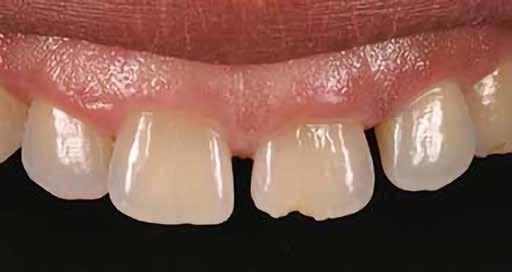

A 19 éves hölgypáciens azzal a kéréssel jelentkezett a rendelőnkbe, hogy szebb fogakat szeretne. Az első konzultáció alkalmával megkérdeztük, hogy mi zavarja leginkább a fogazatának jelenlegi megjelenésében, valamint azt is megbeszéltük vele, hogy milyen végeredmény elérése esetén lenne maradéktalanul elégedett. Ebben az esetben a kezelési célokat az alábbiakban határoztuk meg:

A páciens fogazata esztétikai megjelenésének és funkcionális működésének a lehető legtöbb, saját foganyag megtartása mellett történő helyreállítása (1. és 3. ábra).

A lehető legideálisabb esztétikai végeredmény elérése érdekében néhány esetben a fogak alakjának módosítá -